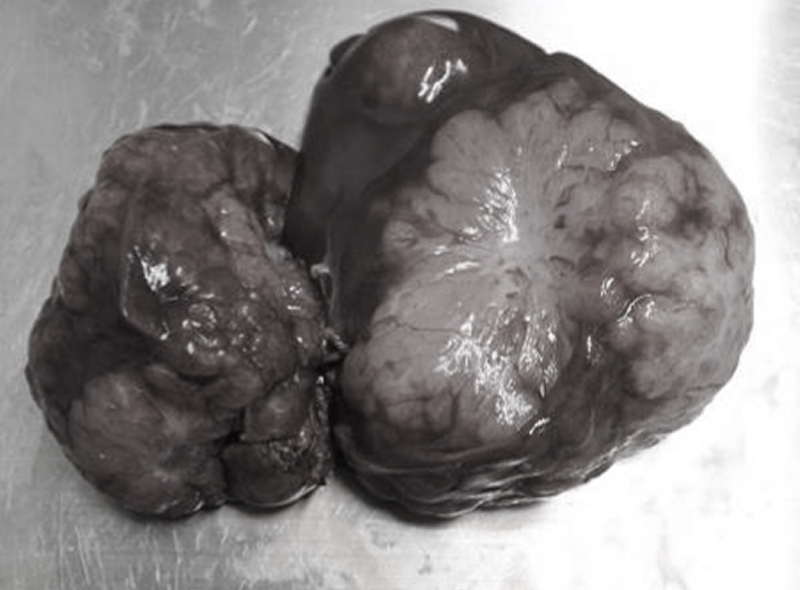

単一の肝葉に形成された腫瘤は肝細胞腺腫や肝細胞がんであることが多く、切除可能であれば予後良好であることが知られています。しかし、手術の難易度の高さから治療を断念されている患者さんの相談を受けます。

当院では術前にCT検査を実施し、手術可否の判断を行い、手術を実施しております。

左肝区域はもちろん、一般的に難易度の高いとされている中央肝区域と右肝区域の手術も実施しております。一度、ご相談ください。

切除された肝臓腫瘍